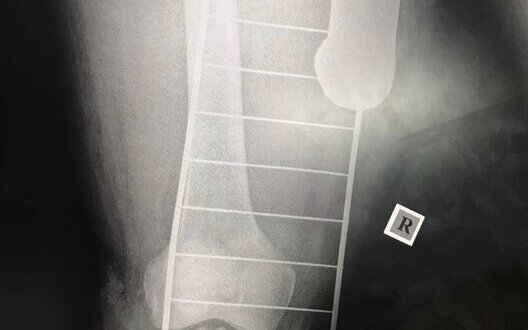

Врачи достали из ноги раненого украинского защитника часть кассетного боеприпаса. ФОТО

В одном из полевых госпиталей врачи изъяли из ноги раненого украинского воина часть кассетного боеприпаса – суббоеприпас. censor.net »